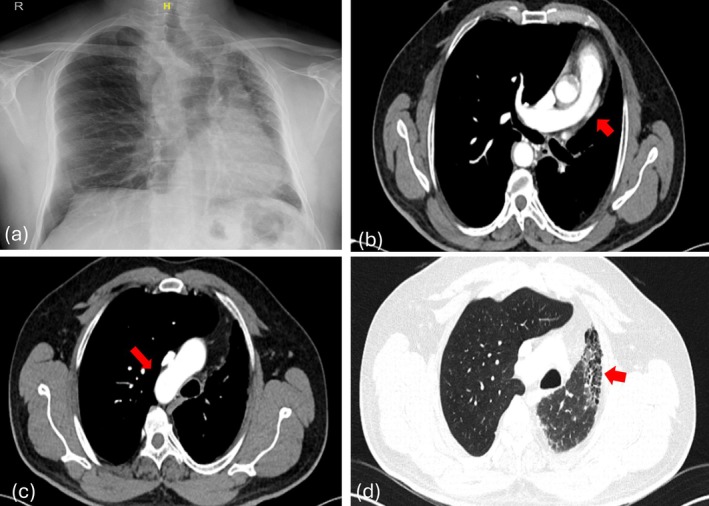

单侧肺动脉闭锁(UPAA)是一种罕见的先天性异常,其特征是缺少一条肺动脉。本文研究了三例UPAA,主要影响右侧,尽管有一例涉及左侧。常见的特征包括咯血,在两例患者中观察到,一例有慢性病史,需要栓塞,另一例是轻微的,最近发病。第三例是在术前评估时偶然发现的。所有病例均表现出不同程度的同侧肺体积缩小和相关间质改变或纤维化。UPAA可无症状或以咯血、反复感染或呼吸困难为表现。诊断依赖于计算机断层肺血管造影(CTPA)或磁共振血管造影(MR)。治疗方法从观察到栓塞或严重病例的全肺切除术。死亡率约为7%,肺动脉高压和出血是主要的预后因素。

Unilateral pulmonary artery atresia (UPAA) is a rare congenital anomaly marked by the absence of one of the pulmonary arteries. This article examines three instances of UPAA, predominantly affecting the right side, although one case involved the left side. Common characteristics included hemoptysis, observed in two patients-one with a chronic history necessitating embolization and another with a mild, recent onset. The third case was identified incidentally during a preoperative evaluation. All cases demonstrated varying degrees of ipsilateral lung volume reduction and associated interstitial changes or fibrosis. UPAA can be asymptomatic or present with hemoptysis, recurrent infections, or breathlessness. Diagnosis relies on computed tomography pulmonary angiography (CTPA) or magnetic resonance (MR) angiography. Management ranges from observation to embolization or pneumonectomy in severe cases. Mortality is around 7%, with pulmonary hypertension and haemorrhage being major prognostic factors.